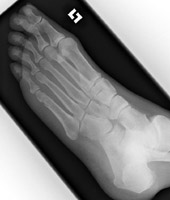

Metatarsal fractures are usually due to direct trauma. Often they are part of the Lisfranc fracture-dislocation spectrum.